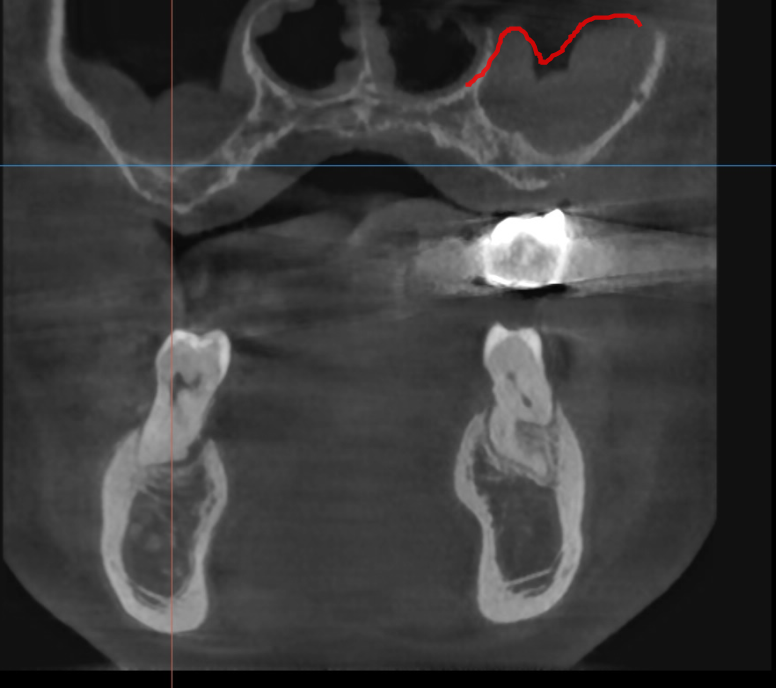

(1) 정밀한 사전 진단

CT 촬영을 통한 정확한 골 상태 분석과 치료 계획 수립이 필수적입니다.

230620 골질 상태까지 나오는 ct

또한 네비게이션 임플란트 시술 방식과 같은것이 결합된다면

조금 더 정확도를 높일 수 있습니다.

뼈가 충분한 부분에 정확한 각도로 식립할 수 있으니까요~